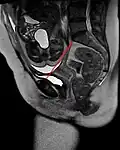

Conjugata vera as measured on sagittal MRI -

| Anteroposterior or conjugate diameter or conjugata vera | Extends from the upper margin of the pubic symphysis to the sacrococcygeal joint; | about 110 mm. |

| Anatomical conjugate | Extends from the pubic symphysis to the promontory; | about 120 mm. |

| Diagonal conjugate | Extends from lower margin of the pubic symphysis to the sacral promontory; | about 130 mm. |